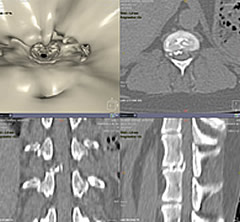

椎間板ヘルニア

石灰化した椎間板物質が脊髄を圧迫し後躯麻痺を起こしていました。

仮想内視鏡モードで脊柱管を覗きました。

3Dサジタルでも石灰化した椎間板物質が、脊柱管内に逸脱しているのが認められます。